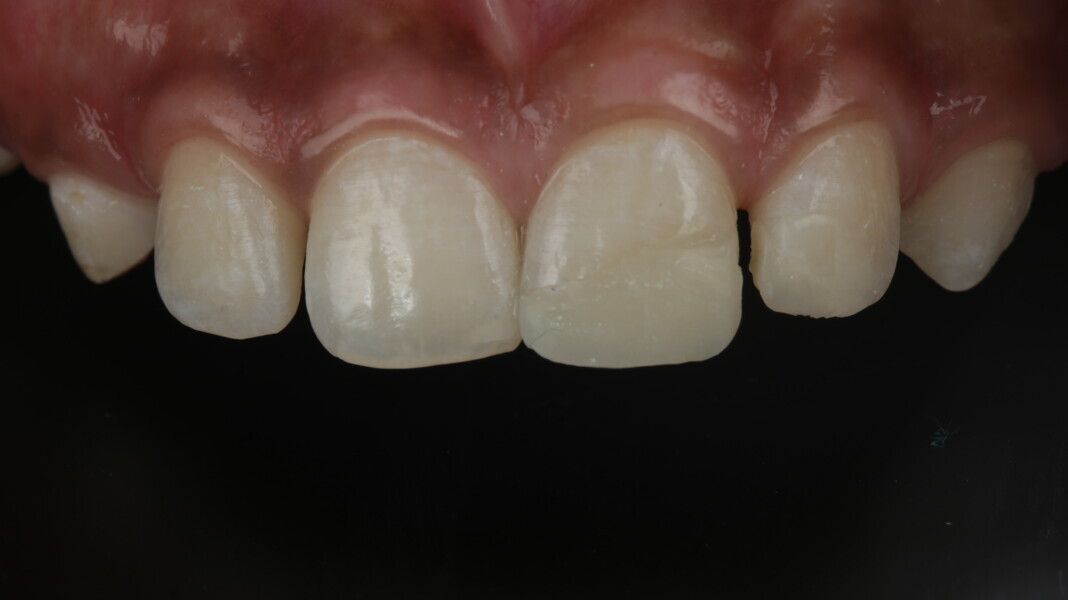

A 10-year-old male patient reported with a complaint of trauma to the upper left central and lateral incisors, involving the enamel and dentin. Direct composite was used in multi-layers and the smile was restored. This article explains detailed steps in the polychromatic layering technique with special emphasis on the finishing and polishing protocol. 3M Espe Filtex Z350 Xt was used with a universal bonding agent.